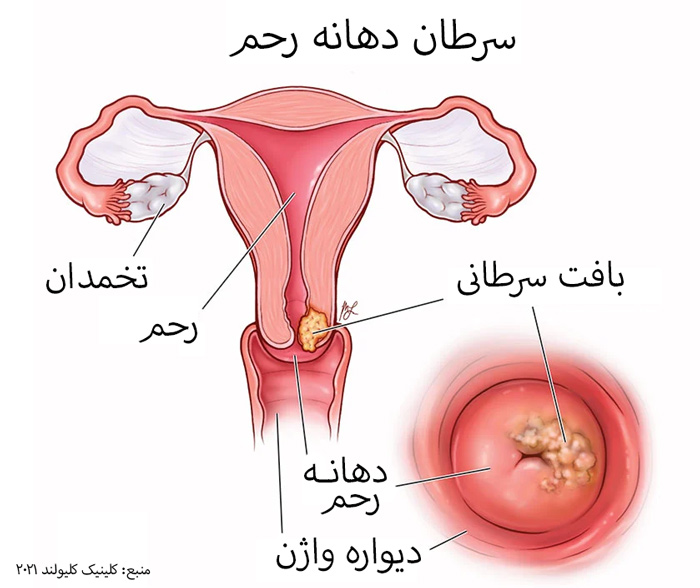

قیمت: 32٬000 تومان - دسته بندی فایل: علوم پزشکیپاورپوینت سرطان دهانه ی رحم

فروش ویژه پاور پوینت حرفه ای سرطان دهانه ی رحم با تخفیف استثنایی فقط 63 هزار تومان تعداد اسلاید: 22 اسلاید